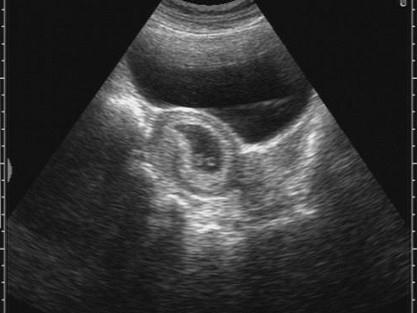

问题 超声检查如图,液性暗区内光环样结构为 ( )

选项 A、脐带 B、羊水 C、羊膜囊 D、卵黄囊 E、胚芽

答案 D